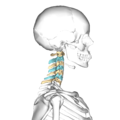

颈椎的典型侧视图。

• 颈椎,侧视图(以蓝色和黄色显示)